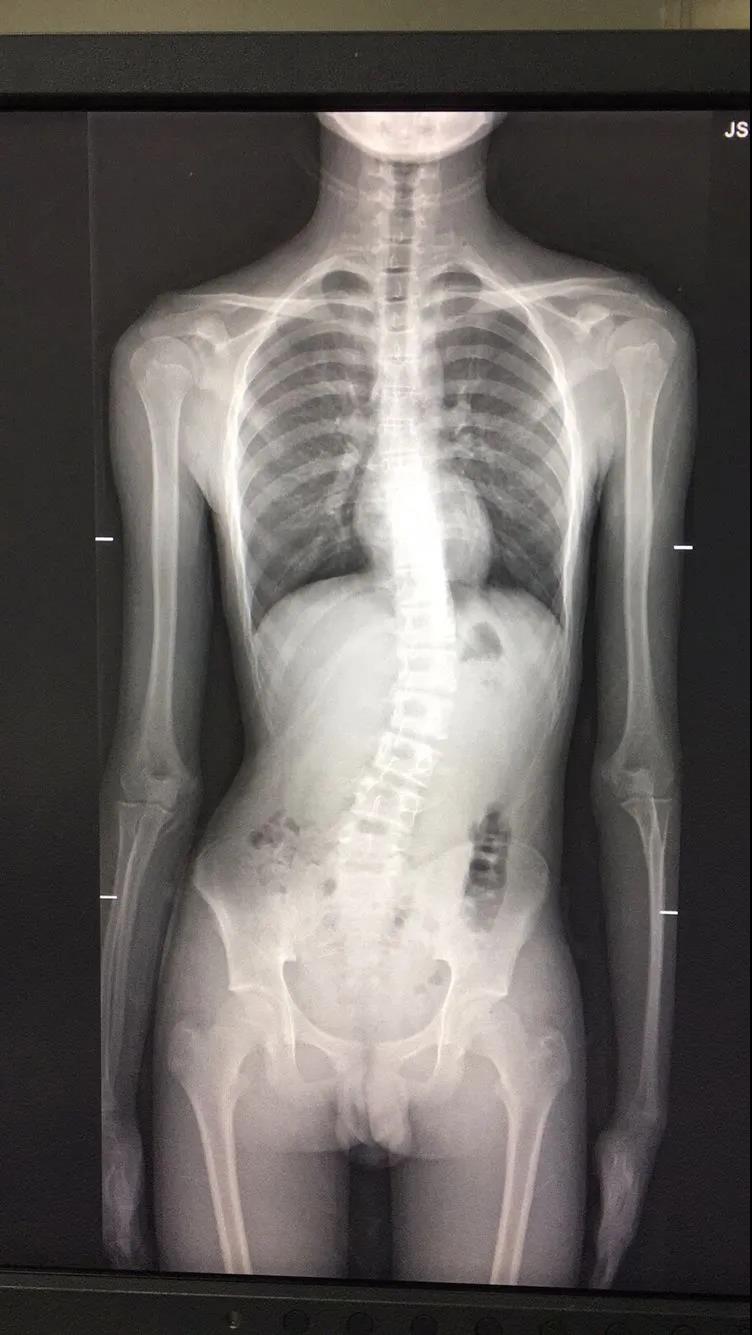

脊柱侧凸俗称脊柱侧弯,它是一种脊柱的三维畸形,包括冠状位、矢状位和轴位上的序列异常。正常人的脊柱如果从正面看有双肩不等高或后面看到有后背左右不平,就应怀疑“脊柱侧凸”。这个时候应拍摄站立位的全脊柱X线片,如果正位X线片显示脊柱有大于10度的侧方弯曲,即可诊断为脊柱侧凸。脊柱侧凸会影响婴幼儿及青少年的生长发育,使身体变形,严重者可以影响心肺功能、甚至累及脊髓,造成瘫痪,脊柱侧凸是危害青少年和儿童的常见疾病,关键是要早发现、早治疗。

小知识:脊柱侧弯,从字面上理解,就是脊柱发生向侧方的弯曲,不直了。如果脊柱在后面看发生了向侧方的弯曲,就要怀疑脊柱侧弯的可能性,家长可以在小孩洗澡的时候注意观察一下:1、肩部是否等高2、背部是否平整 如果在生活中,发现小孩有上述情况,一定要到专业的影像中心拍摄全脊柱X线片 简单方便 及早诊断 切勿耽误治疗。徐州市第一人民医院影像中心全脊柱摄影检查为脊柱侧弯病患 保驾护航 。